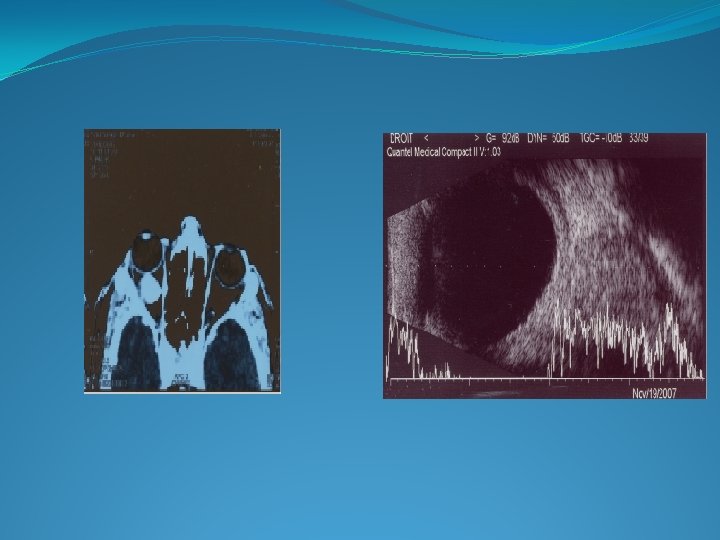

� IMAGERIE: -echographie: masse très échogène calcification extension des lésions -TDM: calcification -IRM: +++extension au NO/cerveau � EVOLUTION: spontanée : envahissement de tout le globe extension extra oculaire métastases(snc , no controlatéral , poumon , os ) DONC bilan d’extension.